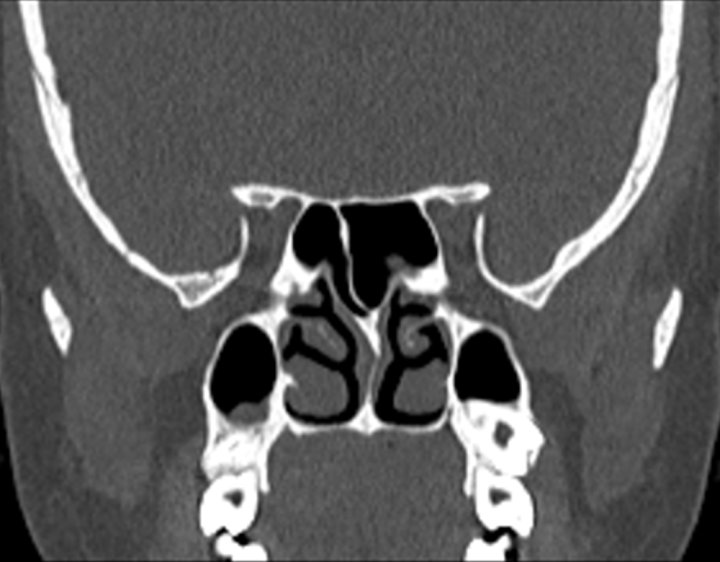

Click any image for labels.